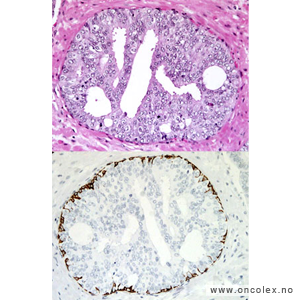

Analyse av vevsprøver

Vevsprøver sendes til histologisk analyse. Analysene kan være avgjørende for hvilken behandling pasienten får. Når patologen undersøker vevsprøvene i mikroskop blir det angitt hvor det er påvist kreft, hvor mange millimeter karsinom det er i hver vevsprøve i forhold til den totale mengde av vevsprøver. Det angis også om det er kribriform vekst, perinevral infiltrasjon og infiltrasjon i fettvev eller sædblærer (vesicula seminalis), hvis dette er kommet med i vevsprøvene. Vevsprøven typebestemmes og graderes (Gleason og/eller ISUP).

95 % av kreftsvulstene i prostata er adenokarsinomer som utgår fra kjertelendestykkene og gangene i prostata. De vokser multifokalt i prostata og gir ofte ingen synlige tumorknuter i mikroskop. Vel 75% av tilfellene oppstår i bakre del av prostata.

Bildeeksempler av vevsprøver

Gleasongraderinger

Ved prostatakreft anvendes et særskilt graderingssystem som ble beskrevet av patologen Donald Gleason i 1966. Dette samsvarer sterkt til prognosen. I motsetning til WHO baserer Gleasongradering/Gleason score (GS) seg kun på kjertlenes arkitektur og cellenes sammensetning, ikke cellenes atypi. De senere årene har ISUP gradering kommet i bruk, det er forsåvidt en forenkling av GS med et tall fra 1-5 hvor ISUP 1 = GS6, ISUP 2 = GS 7a, ISUP 3 = GS7b, ISUP 4 = GS8 og ISUP 5 = GS 9 og 10.